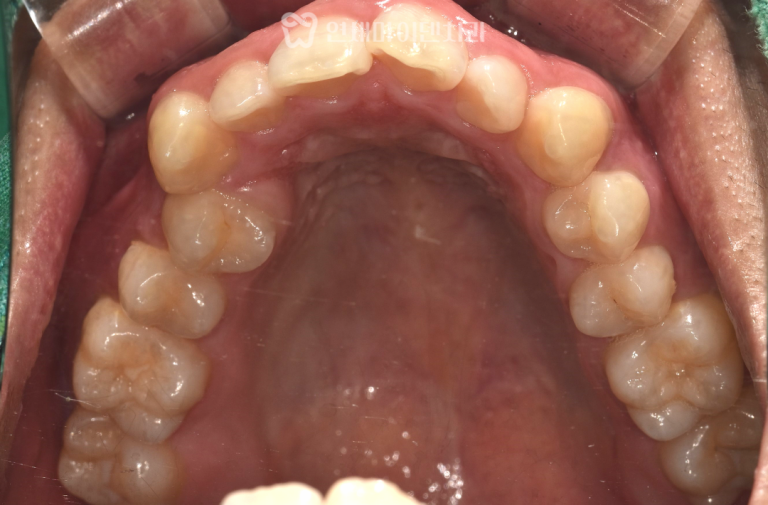

상악 좌측 제2대구치는 초기에는

신경치료 후 크라운 수복까지 완료하였으나,

7개월 후 재내원 시 입천장 쪽 치근 주위의 치조골이

완전히 소실된 상태였습니다.

외측 치근이 정상으로 보여 판단이 어려웠던 케이스로,

세균막이 치근 내면 깊숙이 형성되어 있었습니다.

이 부위는 즉시 임플란트가 불가능하다고 판단하여

우선 발치와 보존술(socket preservation) 을 시행하였습니다.

4개월 후 잇몸과 뼈가 충분히 재생되어

상악동과 연계한 지연 임플란트를 식립하여 마무리하였습니다.